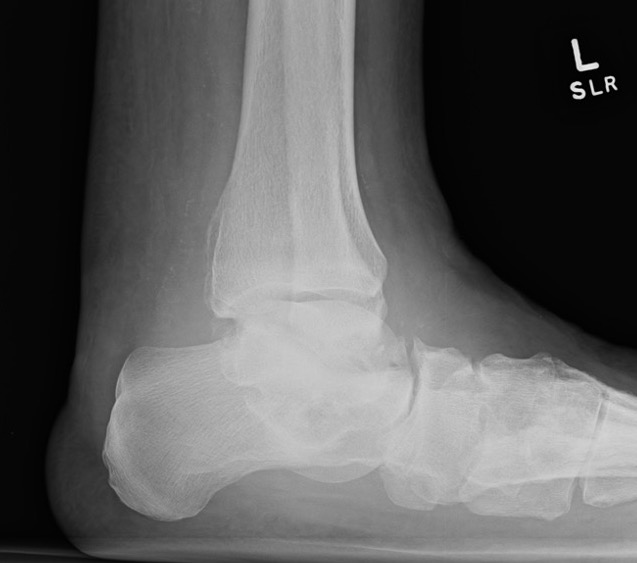

Xray

Midfoot collapse

Midfoot collapse and rocker bottom foot with small ulcer

Midfoot collapse with subluxation of midtarsal joints

Hindfoot collapse with ulcer